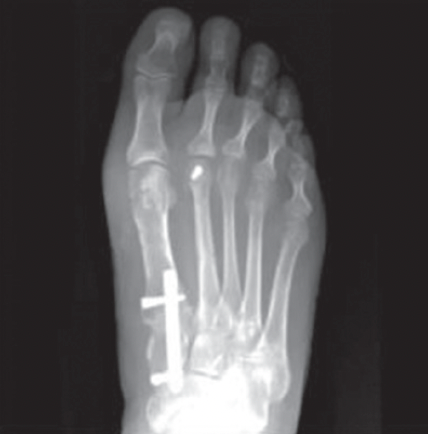

BEFORE

AFTER